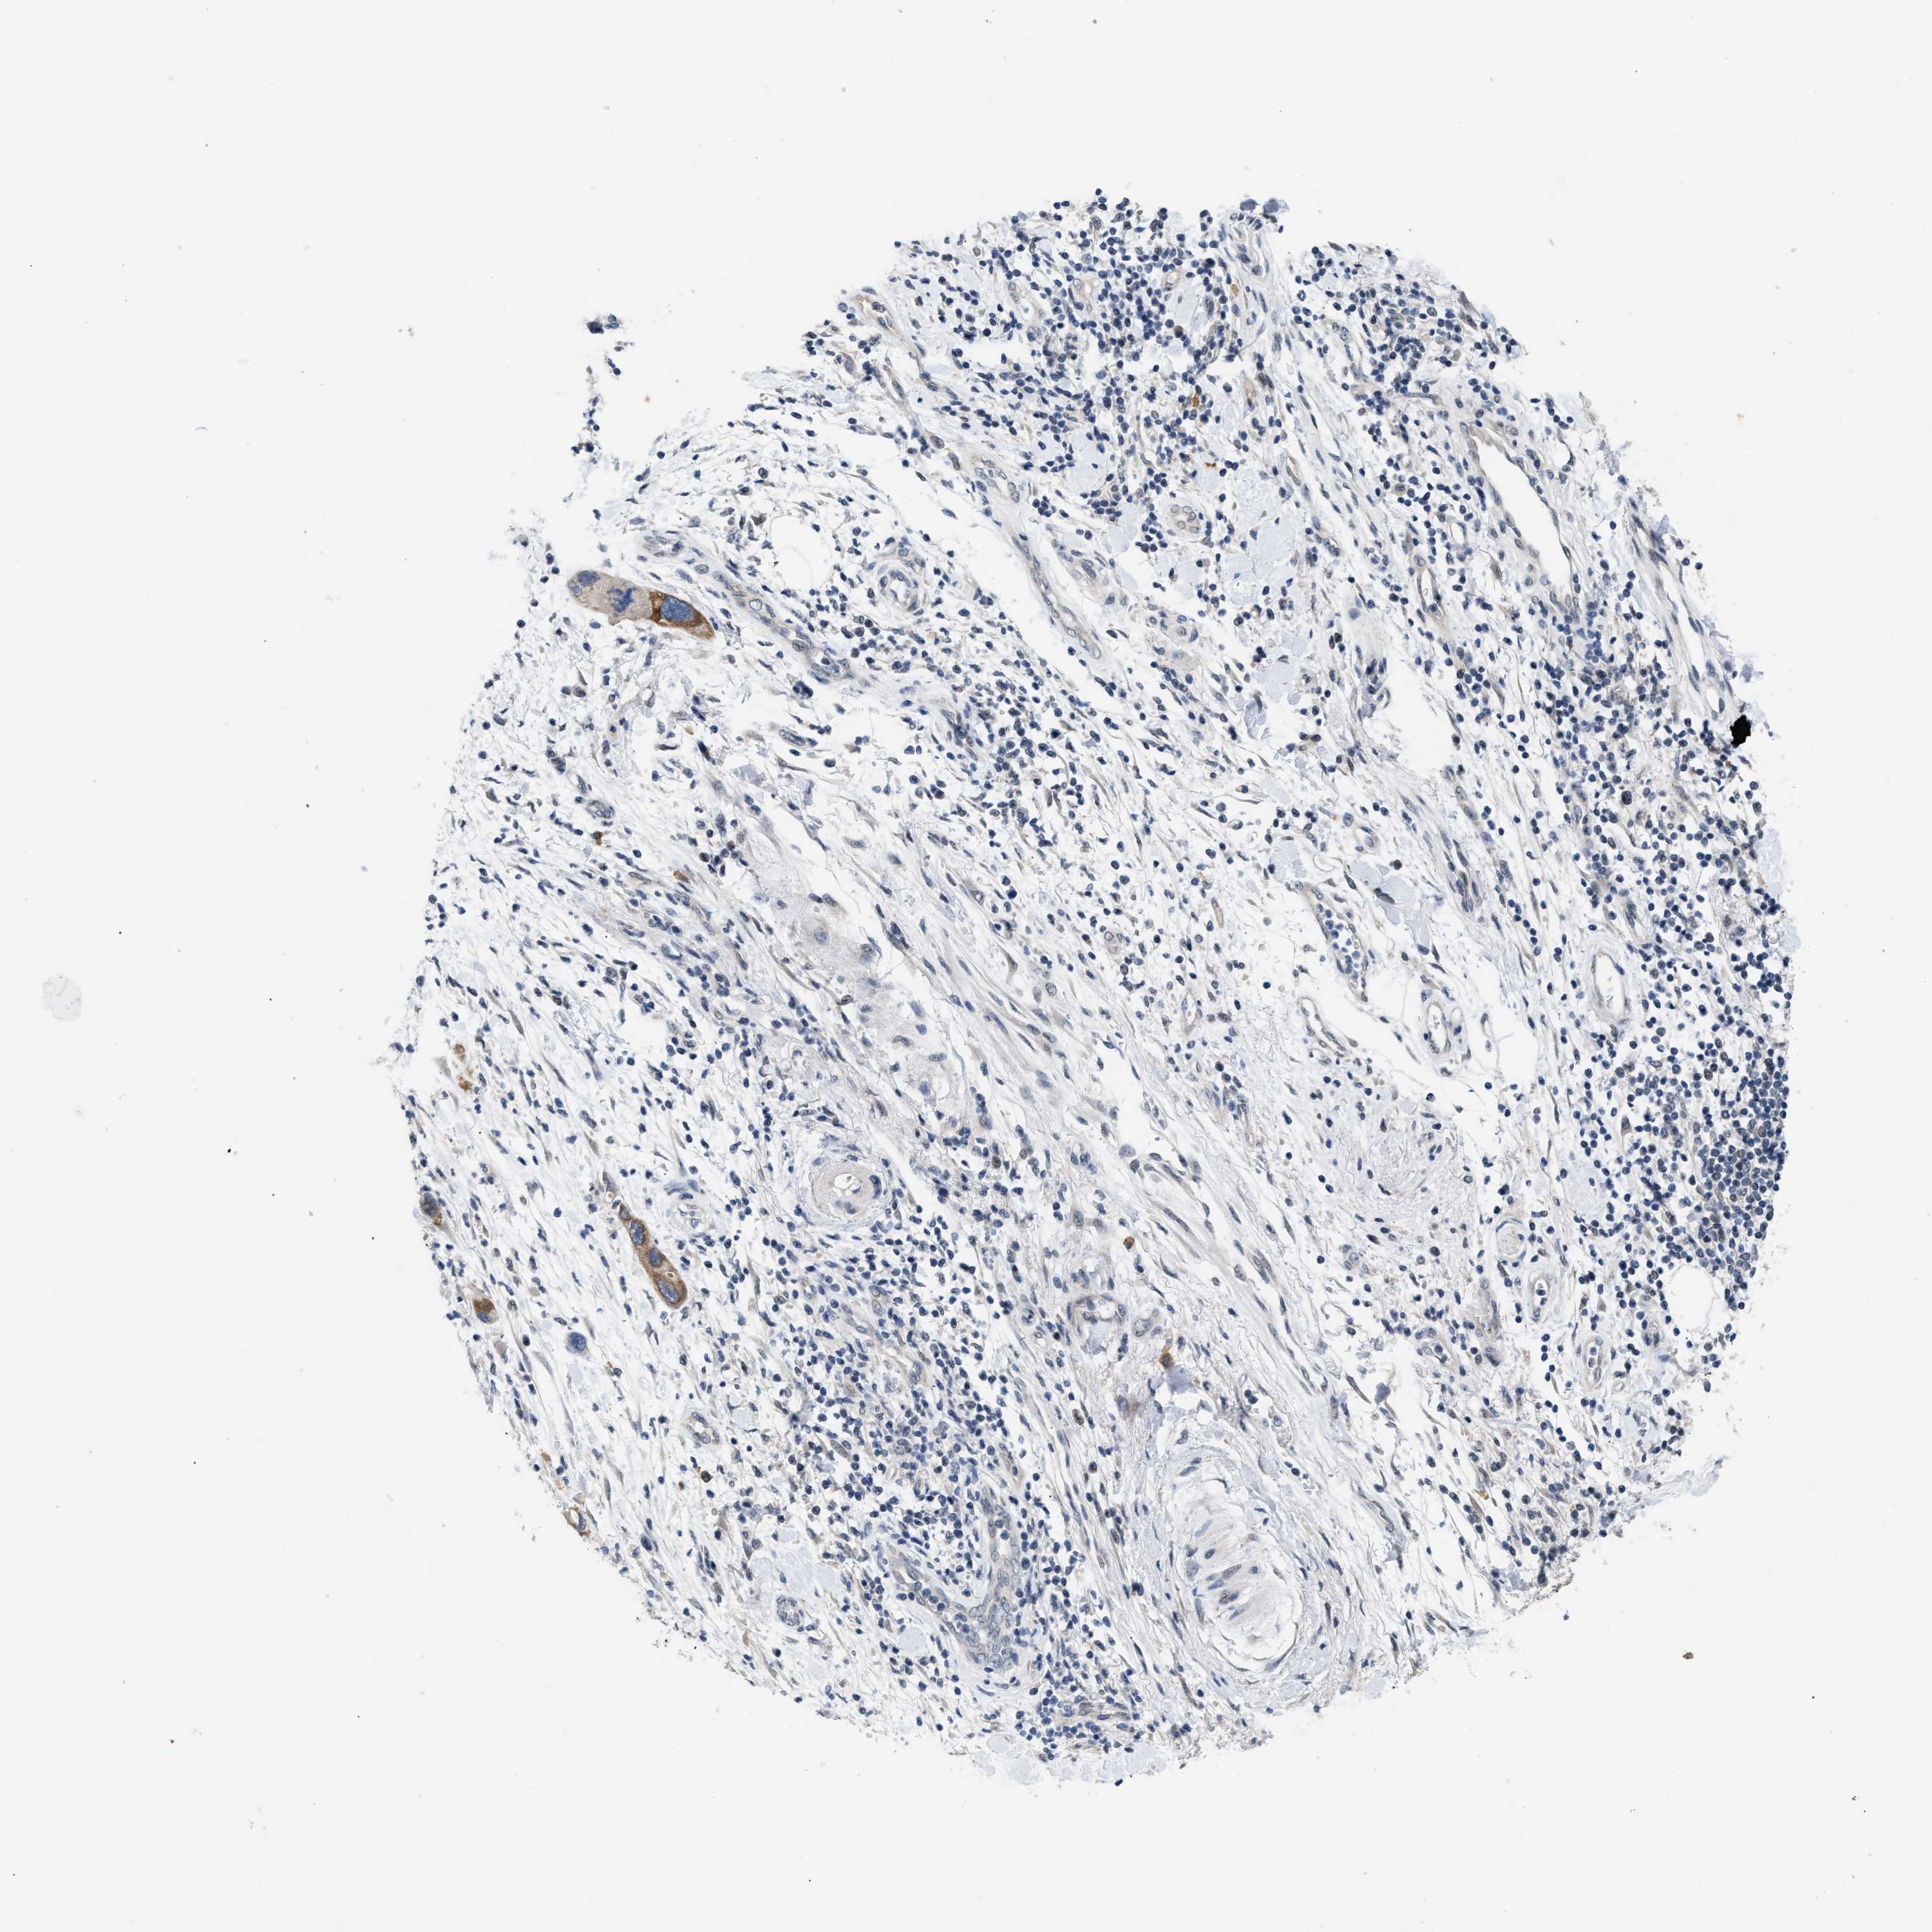

PANCREATIC CANCER - Protein expressioni

A mouse-over function shows sample information and annotation data. Click on an image to view it in a full screen mode. Samples can be filtered based on level of antibody staining by selecting one or several of the following categories: high, medium, low and not detected. The assay and annotation is described here.

Note that samples used for immunohistochemistry by the Human Protein Atlas do not correspond to samples in the TCGA dataset.

Antibody stainingi

Antibody staining in the annotated cell types in the current human tissue is reported as not detected, low, medium, or high, based on conventional immunohistochemistry profiling in selected tissues. This score is based on the combination of the staining intensity and fraction of stained cells.

Each image is clickable and will lead to virtual microscopy that enables deeper exploration of all samples and also displays staining intensity scores, fraction scores and subcellular localization as well as patient and tissue information for each sample.

Antibody CAB020802

Staining

High

Medium

Low

Not detected

Intensity

Strong

Moderate

Weak

Negative

Quantity

>75%

75%-25%

<25%

None

Location

Nuclear

Cytoplasmic/membranous

Cytoplasmic/membranous,nuclear

Adenocarcinoma, NOS